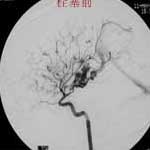

二、脑动静脉畸形(AVM)

---- Spetzler对AVM的分级方法已越来越多地被人们接纳和采用。脑AVM最危险的症状之一是出血。AVM每年的出血率为 3%~4%,第一年内再出血约6%。每次出血的致残率为30%,病死率为12.5%,而积极治疗的总残废率加病死率在10%以下。

---- 血管内栓塞对于单支或少数供血动脉的AVM,特别是新近出血的病例,可以达到微侵袭、痛苦小、疗效迅速的目的。 近来改变栓塞方式,将导管直接放置 畸形血管团内,注射NBCA胶,可使畸形团的解剖 治愈率提高至27%。再加上更细、超 滑的微导管问世,栓塞的并发症更为降低。针对大型、功能区 的AVM栓 塞可缩小其体积,改善血液动力学分布,以利于显 微外科技术切除或放射外科治疗,是后二者的重要辅助手段。